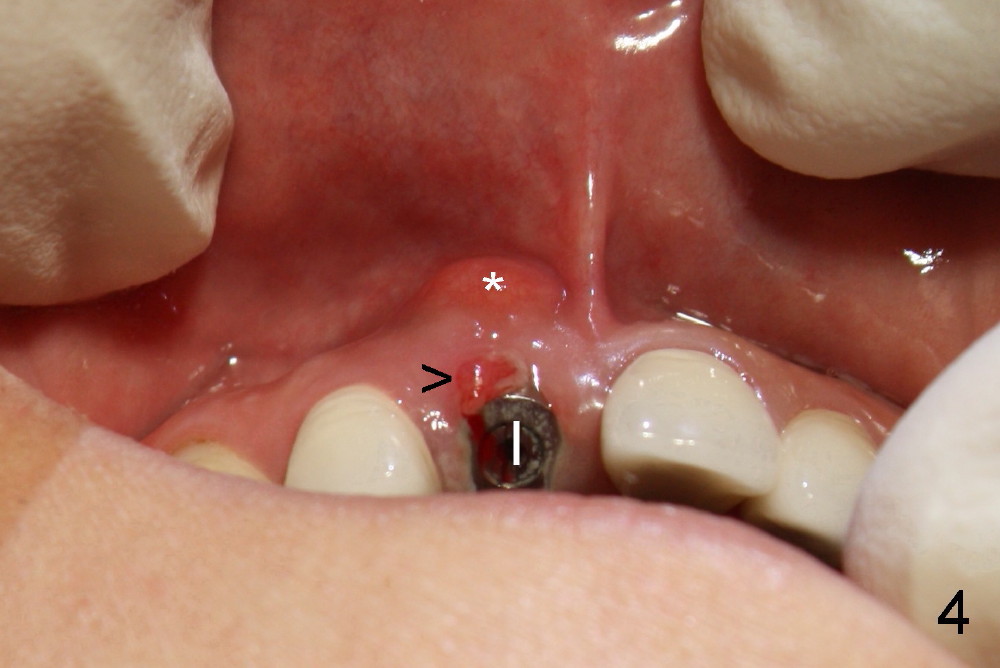

A 44-year-old lady has fractured #8 and agrees to have the tooth extracted after failure of recementation (Fig.1).  Pre-implantation X-ray shows minimal periapical radiolucency (Fig.2: >).  A 5x20 Tatum tapered implant is placed immediately after extraction (Fig.3: I).  Perio dressing is placed and a flipper is delivered.